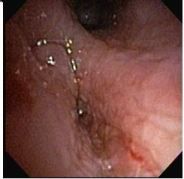

The patient underwent flexible bronchoscopy, which revealed a foreign body in the intermediate bronchus (Figure 1). The foreign body, which was found to be a piece of bone that the patient had aspirated while eating, was removed through the tracheostomy site with the bronchoscope. The bronchus area appeared edematous and erythematous (Figure 2). She was slowly weaned off the ventilator as her lung condition improved.